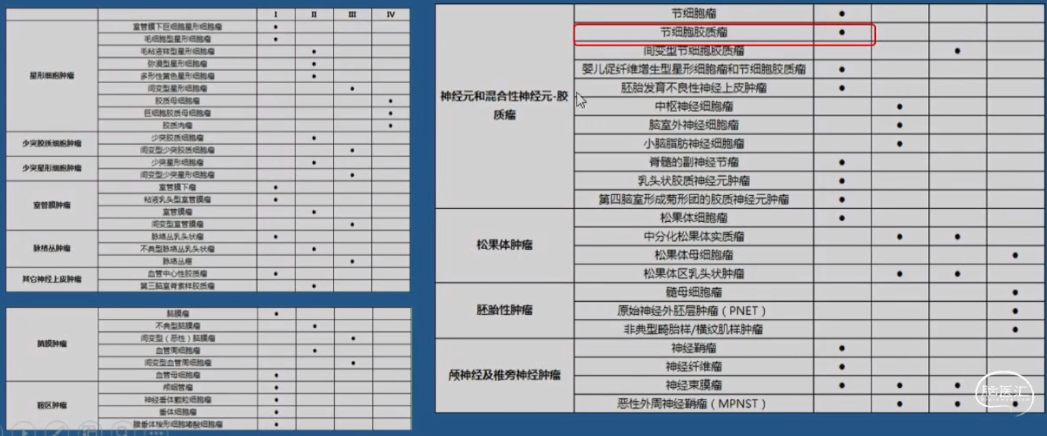

生长缓慢的肿瘤更容易有癫痫,特别是神经胶质发育性肿瘤(Neuroglial developmental tumors)

神经胶质发育性肿瘤(Neuroglial developmental tumors)

•良性的病程,复发和恶变罕见

•癫痫发生率90%-100%

•又被称为低级别癫痫相关性肿瘤(low-grade epilepsy-associated tumors LEAT)

•最常见为胚胎发育不良性神经上皮肿瘤(DNETs)和神经节神经胶质瘤(GGs),是一种特殊的具有高度致痫性的肿瘤

•神经节细胞胶质瘤Gangliogliomas(GG)

•归类:神经元和神经元-神经胶质肿瘤类,WHO Ⅰ级